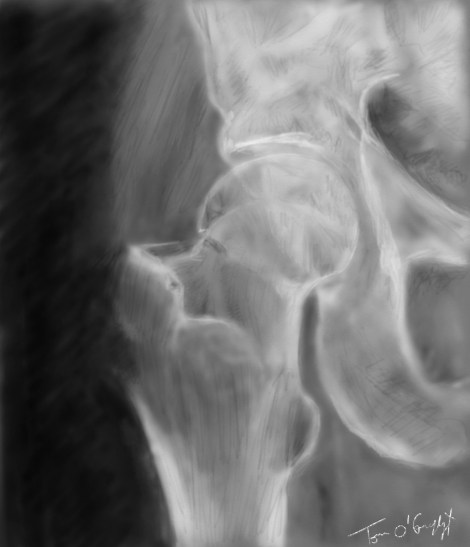

fracture col femur radiographie

fracture du col du fémur type 1 de Garden, déplacement en varus de la tête fémorale

Publié le 3 décembre 2015 à 1030 × 1200 dans Fracture du col du fémur